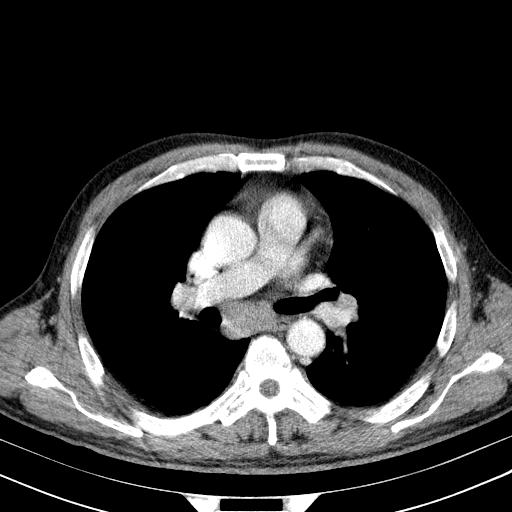

先行ct平扫,纵膈内多发软组织影,ct值约为36hu,以下为增强扫描和腹部平扫。

经典?纵膈多发肿大淋巴结。腹膜后未见异常。

还见胃窦壁增厚!转移亦有可能!

1)考虑淋巴瘤。2)双侧少量胸腔积液。